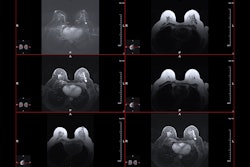

They integrated MRE into a biopsy coil (Siemens Healthineers) for integration of data gathering within standard breast MRI. The team acquired data using a 1.5-tesla MRI system (Aera, Siemens throughout a seven-minute scan using a 3D MRE gradient echo sequence. The team noted that this allowed for non-invasive quantification of tissue biomechanics over 16 consecutive slices at 36Hz mechanical vibration with an isotropic spatial resolution of 3 mm.

The study included 41 women with 205 individual scans. Scans were performed before (1.1) and during (2.1) chemotherapy.